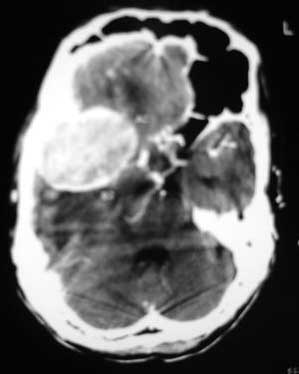

头痛头晕,摔倒两次,肌力基本正常,双手脚颤抖。肺结核。骨窗未见骨质异常。

颅底类圆形肿块,

边缘光整,

强化明显,

考虑脑膜瘤。

脑膜瘤可能性大,强化明显,水肿少[emb6]

水肿非常明显,侧脑室左移非常明显,平扫病灶稍高密度。

问题在于症状不明显,而ct表现明显,是否应考虑胶质瘤(3-4级)?

肿瘤位于中颅窝,宽基底与颞骨或蝶骨大翼相连,平扫呈稍高密度,增强后均匀明显强化,肿瘤周围水肿明显,中线结构移位。我认为是脑膜瘤,其压迫大脑中浅静脉,导致静脉回流受阻,引起阻塞性脑水肿。

肿快具备脑外肿瘤的特征,且明显均匀强化,中颅凹脑膜瘤!

右颅中窝相当于颞下回位置类圆形肿块,明显强化,厚壁,钙化?所见图层周围水肿不明显。为何不完整上传图像?

不支持脑膜瘤的地方是:骨窗未见骨改变(为何不上传?),厚壁,象是钙化。

右侧中颅窝见类圆形的密度增高影(大小待定),增强后均匀明显强化,肿块周围环绕低密度的水肿带,脑中线移位。脑膜瘤可能性大,胶质瘤不能除外;脑水肿。